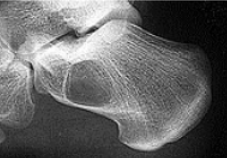

| What disease is this? | Sever's disease |